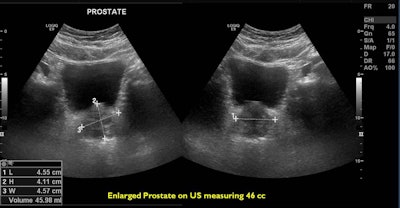

A 66-year-old patient with an International Prostate Symptom Score (IPSS) of 29 and prostate volume of 46 cc. All images courtesy of Dr. Jamal Al Deen Alkoteesh.